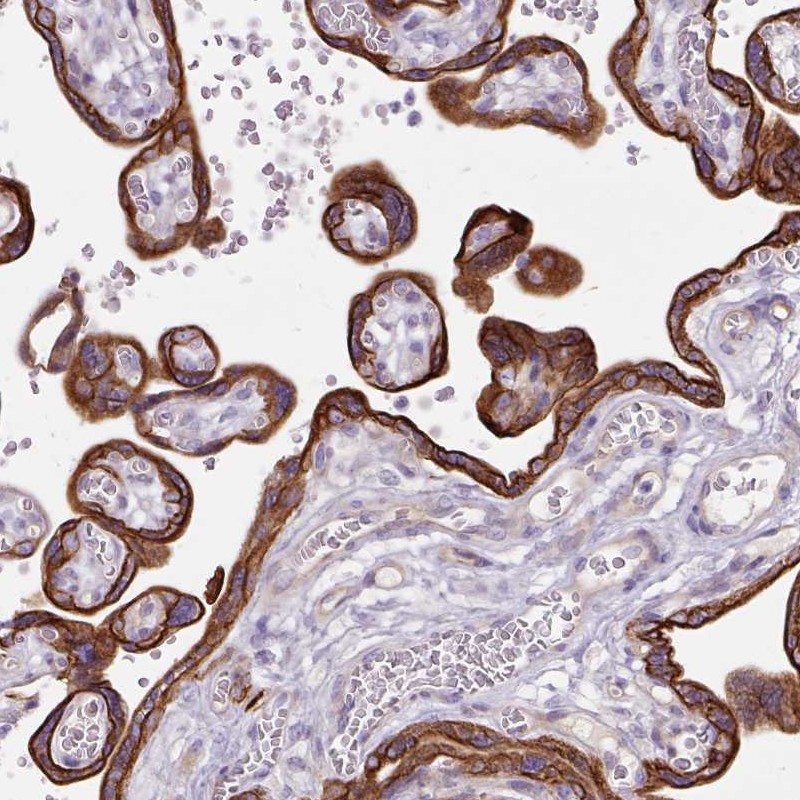

Immunohistochemical staining of human placenta shows cytoplasmic and membranous positivity in trophoblastic cells.